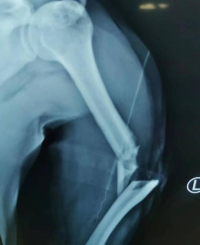

通过X光片检查显示李大哥左上臂为“肱骨开放性骨折、左尺桡骨骨折”,郑大伟主任迅速组织科室展开讨论,为其制定个性化手术方案。

随后,郑大伟主任、李刚、刘绍利医生手术团队对患者行“左上臂清创骨折复位外固定血管神经肌肉撕脱皮肤修复术”,手术紧张有序地进行,首先对撕裂的伤口皮肤进行修整清创后探查发现左肱骨粉碎性骨折,清除游离碎骨片及血凝块后对断端进行复位后吻合血管动脉,修复断裂的肌肉组织后,手术顺利结束!